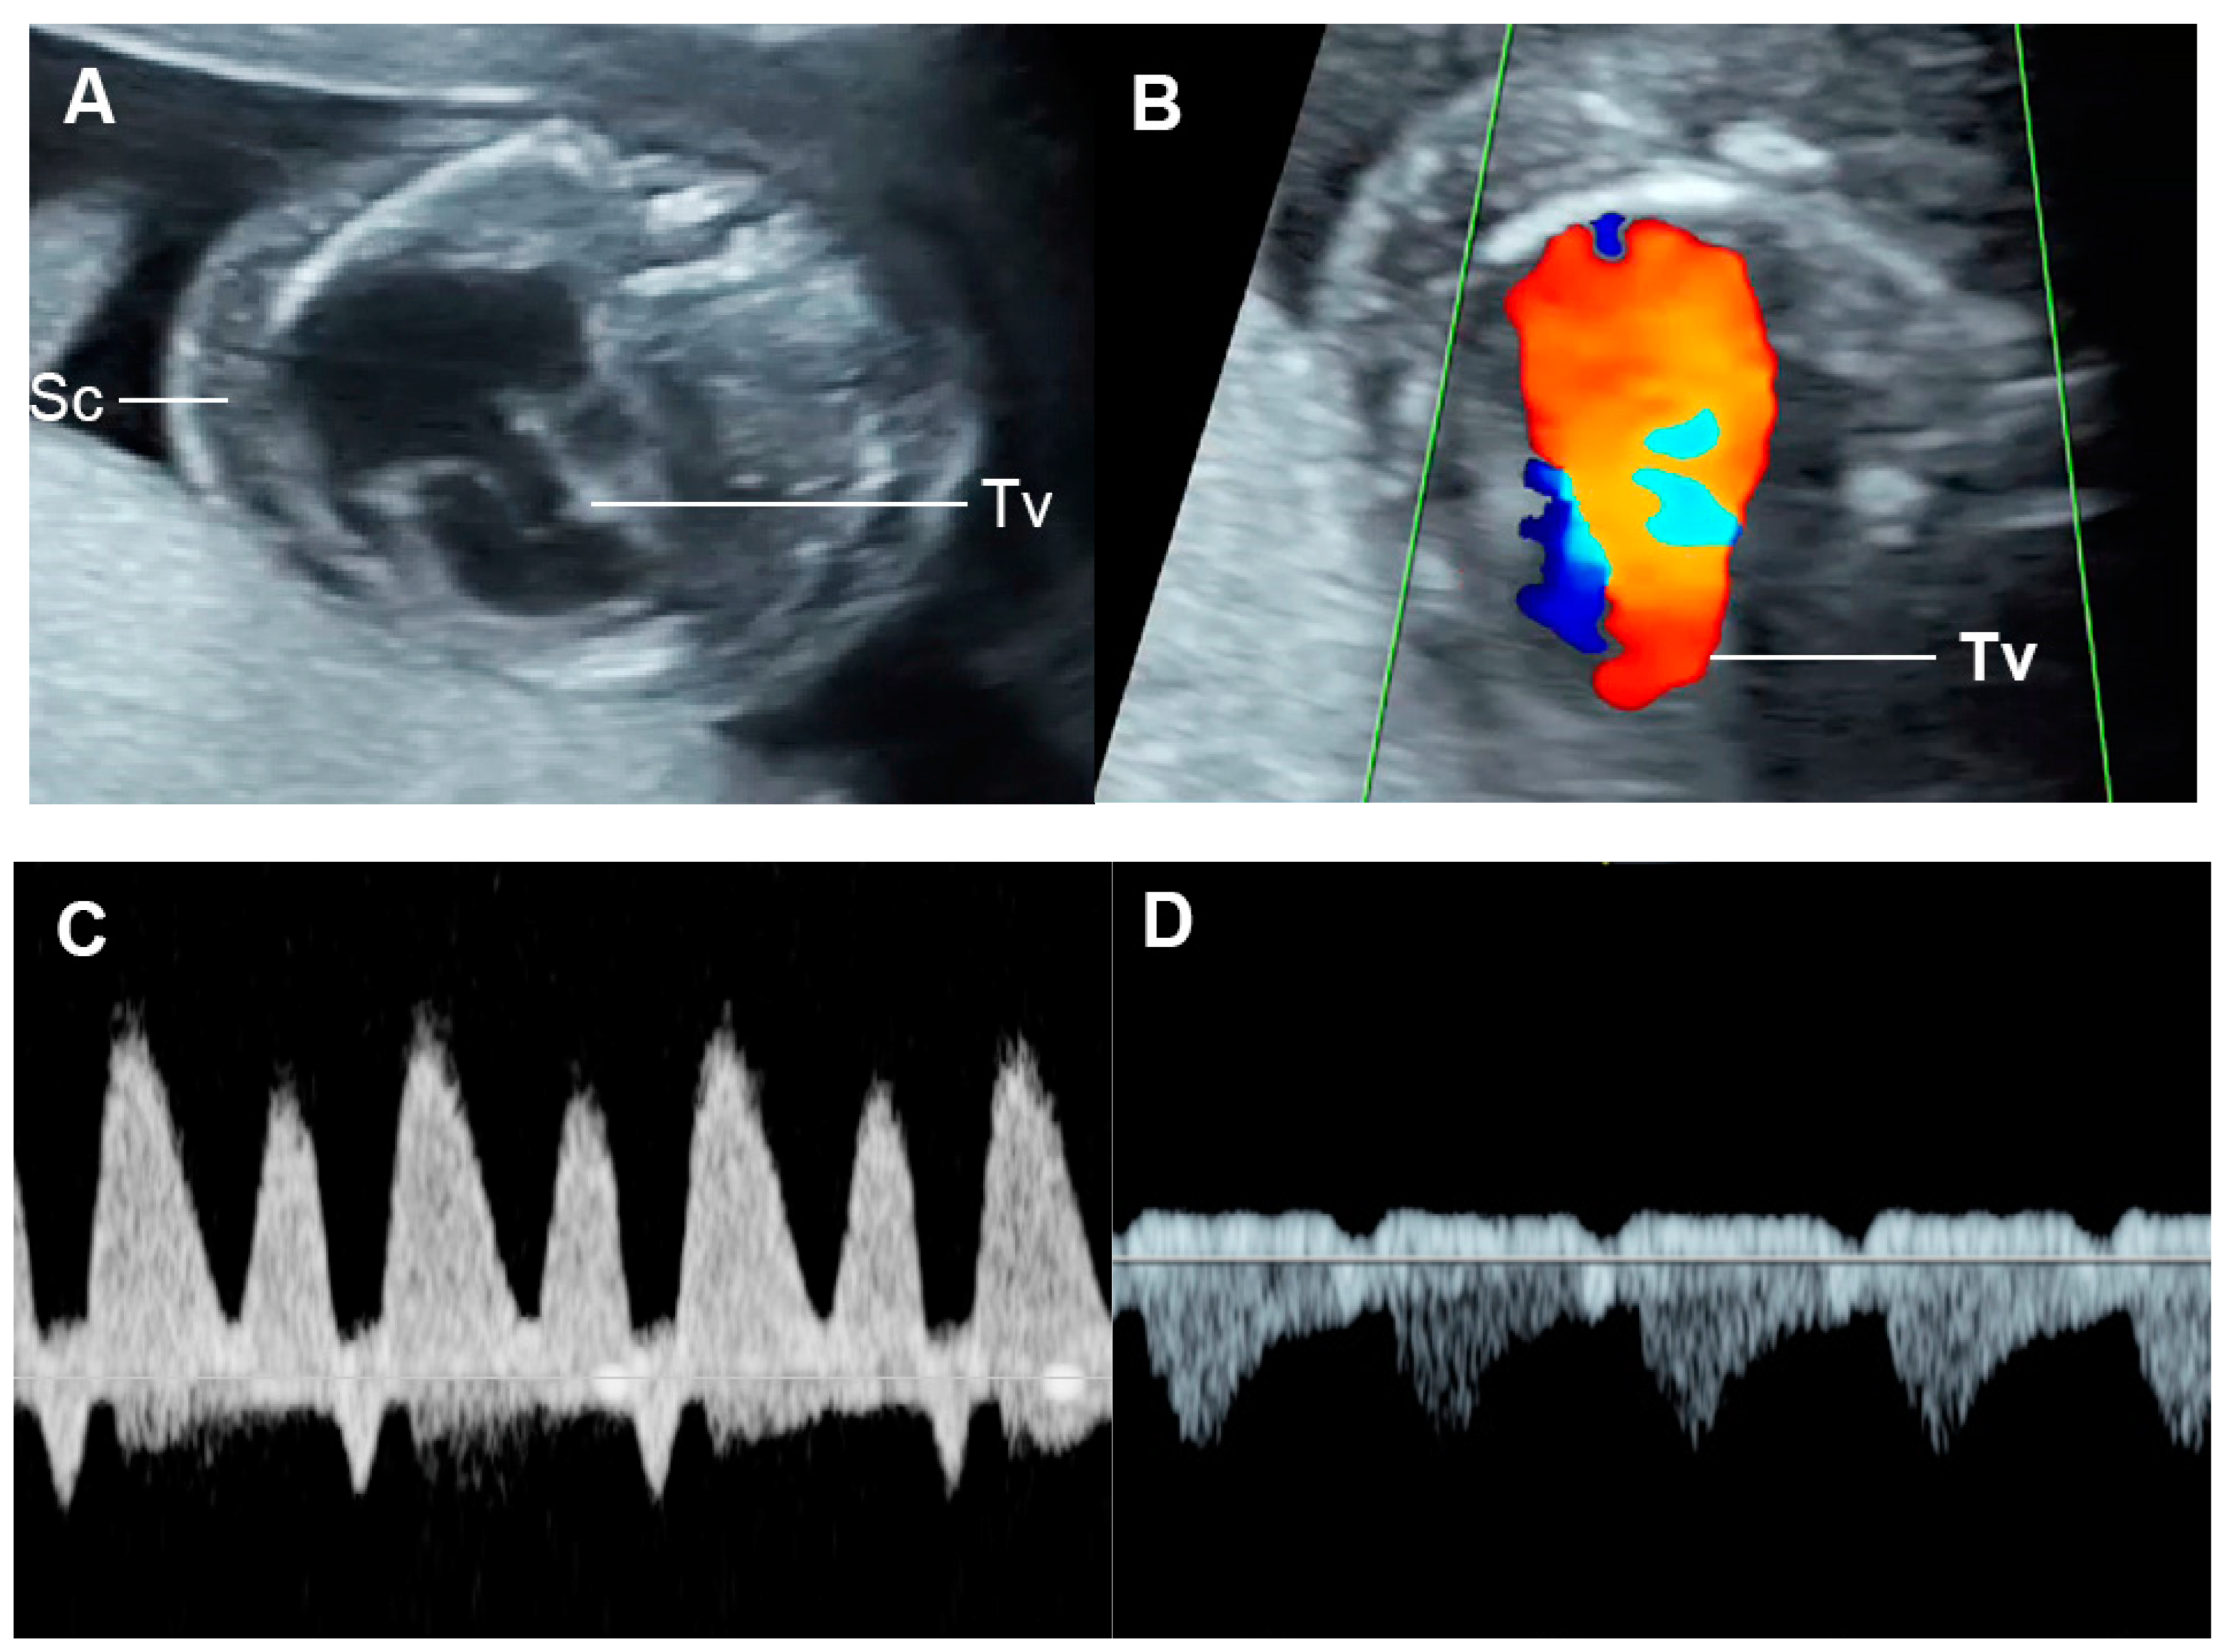

4.3. Fetal Valve Competency

4.6. Ventricular Inflow

4.7. Systemic Venous Pressure